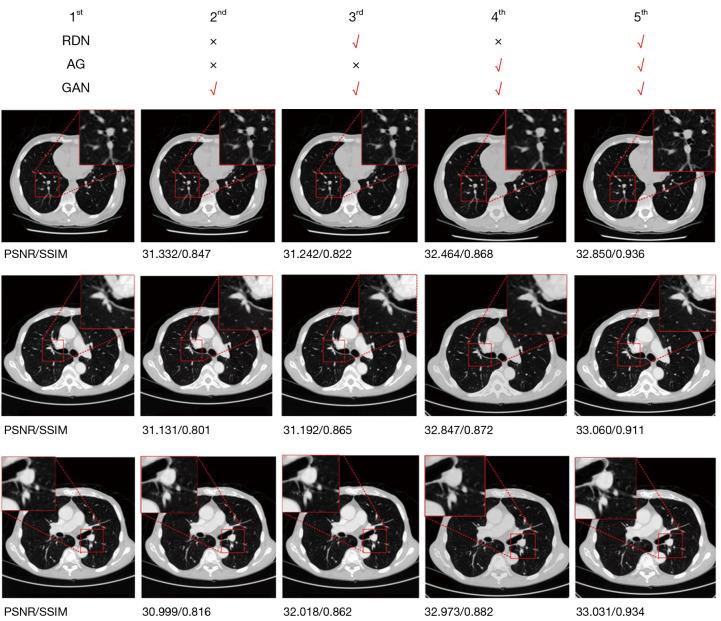

The FRDAGAN method is based on the generative adversarial network (GAN). First, the feature information of different layers is fully utilized by residual dense blocks to prevent gradient decay. Second, the attention gate (AG) network is used to suppress the noise information and improve the signal-to-noise ratio. Finally, a hybrid loss function is used to prevent vanishing or exploding gradients in the network.

On the Luna16 dataset, using single images, the quantitative SR results, peak signal-to-noise ratio (PSNR), and mean structural similarity index measure (SSIM) were 31.257/0.964, 33.558/0.968, and 34.201/0.882, respectively. While on the brain magnetic resonance imaging (MRI) dataset, those values were 34.220/0.874, 35.735/0.885, and 35.854/0.908, respectively. The proposed method showed obvious enhancement compared to the other methods on the Luna16 and brain MRI test data sets, and the PSNR and SSIM values reached 33.005±0.157, 0.938±0.028, and 35.270±0.183, and 0.889±0.024, respectively. The uniform resource locator (URL) for Luna16 is https://luna16.grand-challenge.org/Download/, and the URL for brain MRI is https://www.kaggle.com/datasets/mateuszbuda/lgg-mri-segmentation.

The FRDAGAN method had better results in terms of the PSNR and SSIM than the other traditional methods, and was more stable in terms of the faster convergence of the loss function. The results showed that the FRDAGAN method is effective and advanced.